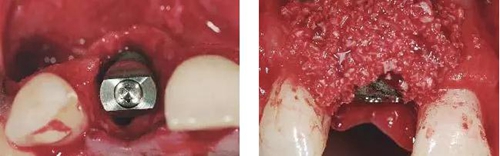

圖6、從磨牙后區(qū)用環(huán)形鉆獲取自體骨,并將其放置在種植體的表面。Geistlich Bio-Oss®骨顆粒混合血液放置在自體骨的外側(cè),防止自體骨的早期吸收。植骨可以穩(wěn)定軟組織外形。

圖7、植骨區(qū)外覆蓋Geistlich Bio-Gide®雙層膠原膜,使得植骨區(qū)更為穩(wěn)定。